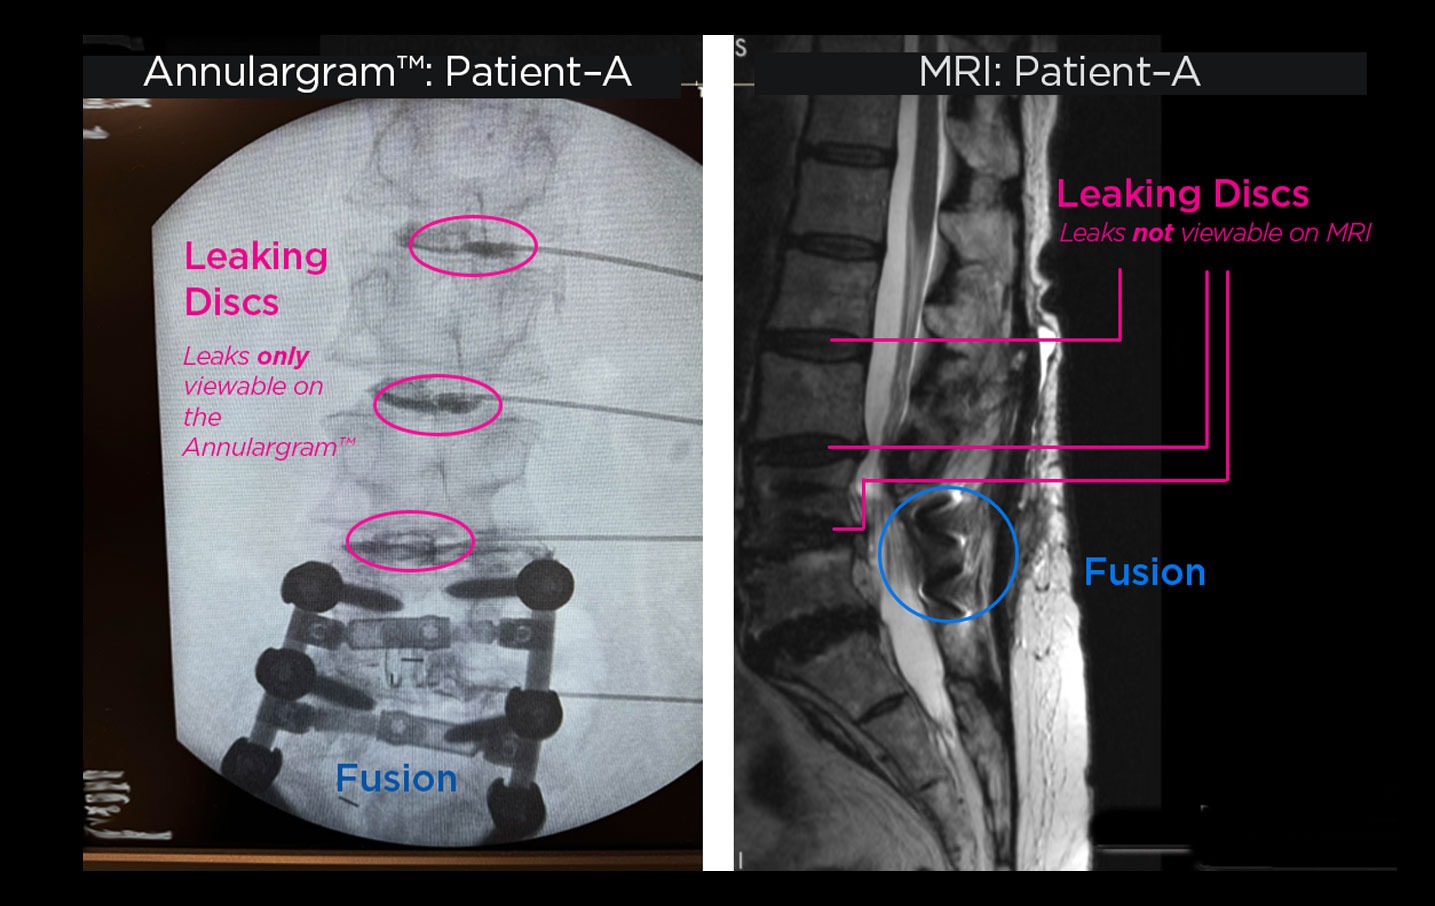

The Annulargram™ and MRI comparison

Figure 01: Comparison of Lumbar spine Annulargram™ and Lumbar spine MRI.

Tears in spinal discs cannot be seen on MRI nor discography. As shown: leaky discs are only visible on the Annulargram.

The DISCSEEL Procedure is an option even if you have previously had spine surgery or regenerative procedures (stem cell or PRP) that have failed.